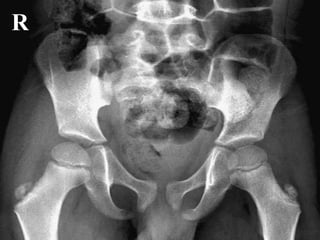

Radiographs of pelvis and hips were obtained

R

Salter Harris I